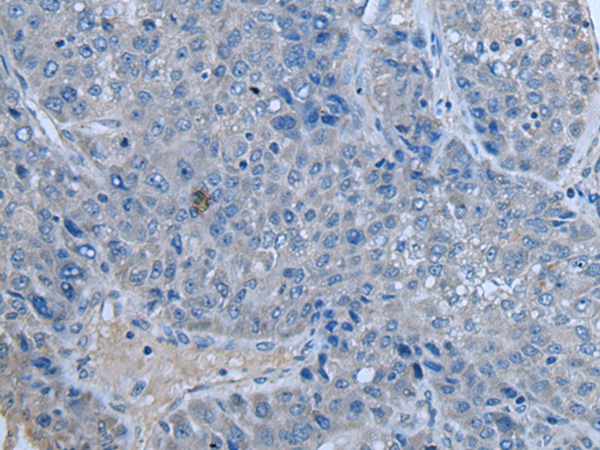

IHC positive control: |

Human lung carcinoma tissue |

IHC Recommend dilution: |

50-100 |